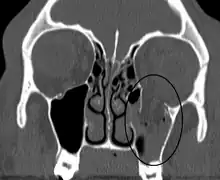

An orbital blowout fracture of the floor of the left orbit.

An orbital blowout fracture is a traumatic deformity of the orbital floor or medial wall that typically results from the impact of a blunt object larger than the orbital aperture, or eye socket.[1] Most commonly this results in a herniation of orbital contents through the orbital fractures.[1] The proximity of maxillary and ethmoidal sinus increases the susceptibility of the floor and medial wall for the orbital blowout fracture in these anatomical sites.[2] Most commonly, the inferior orbital wall, or the floor, is likely to collapse, because the bones of the roof and lateral walls are robust.[2] Although the bone forming the medial wall is the thinnest, it is buttressed by the bone separating the ethmoidal air cells.[2] The comparatively thin bone of the floor of the orbit and roof of the maxillary sinus has no support and so the inferior wall collapses mostly. Therefore, medial wall blowout fractures are the second-most common, and superior wall, or roof and lateral wall, blowout fractures are uncommon and rare, respectively. They are characterized by double vision, sunken ocular globes, and loss of sensation of the cheek and upper gums from infraorbital nerve injury.[3]